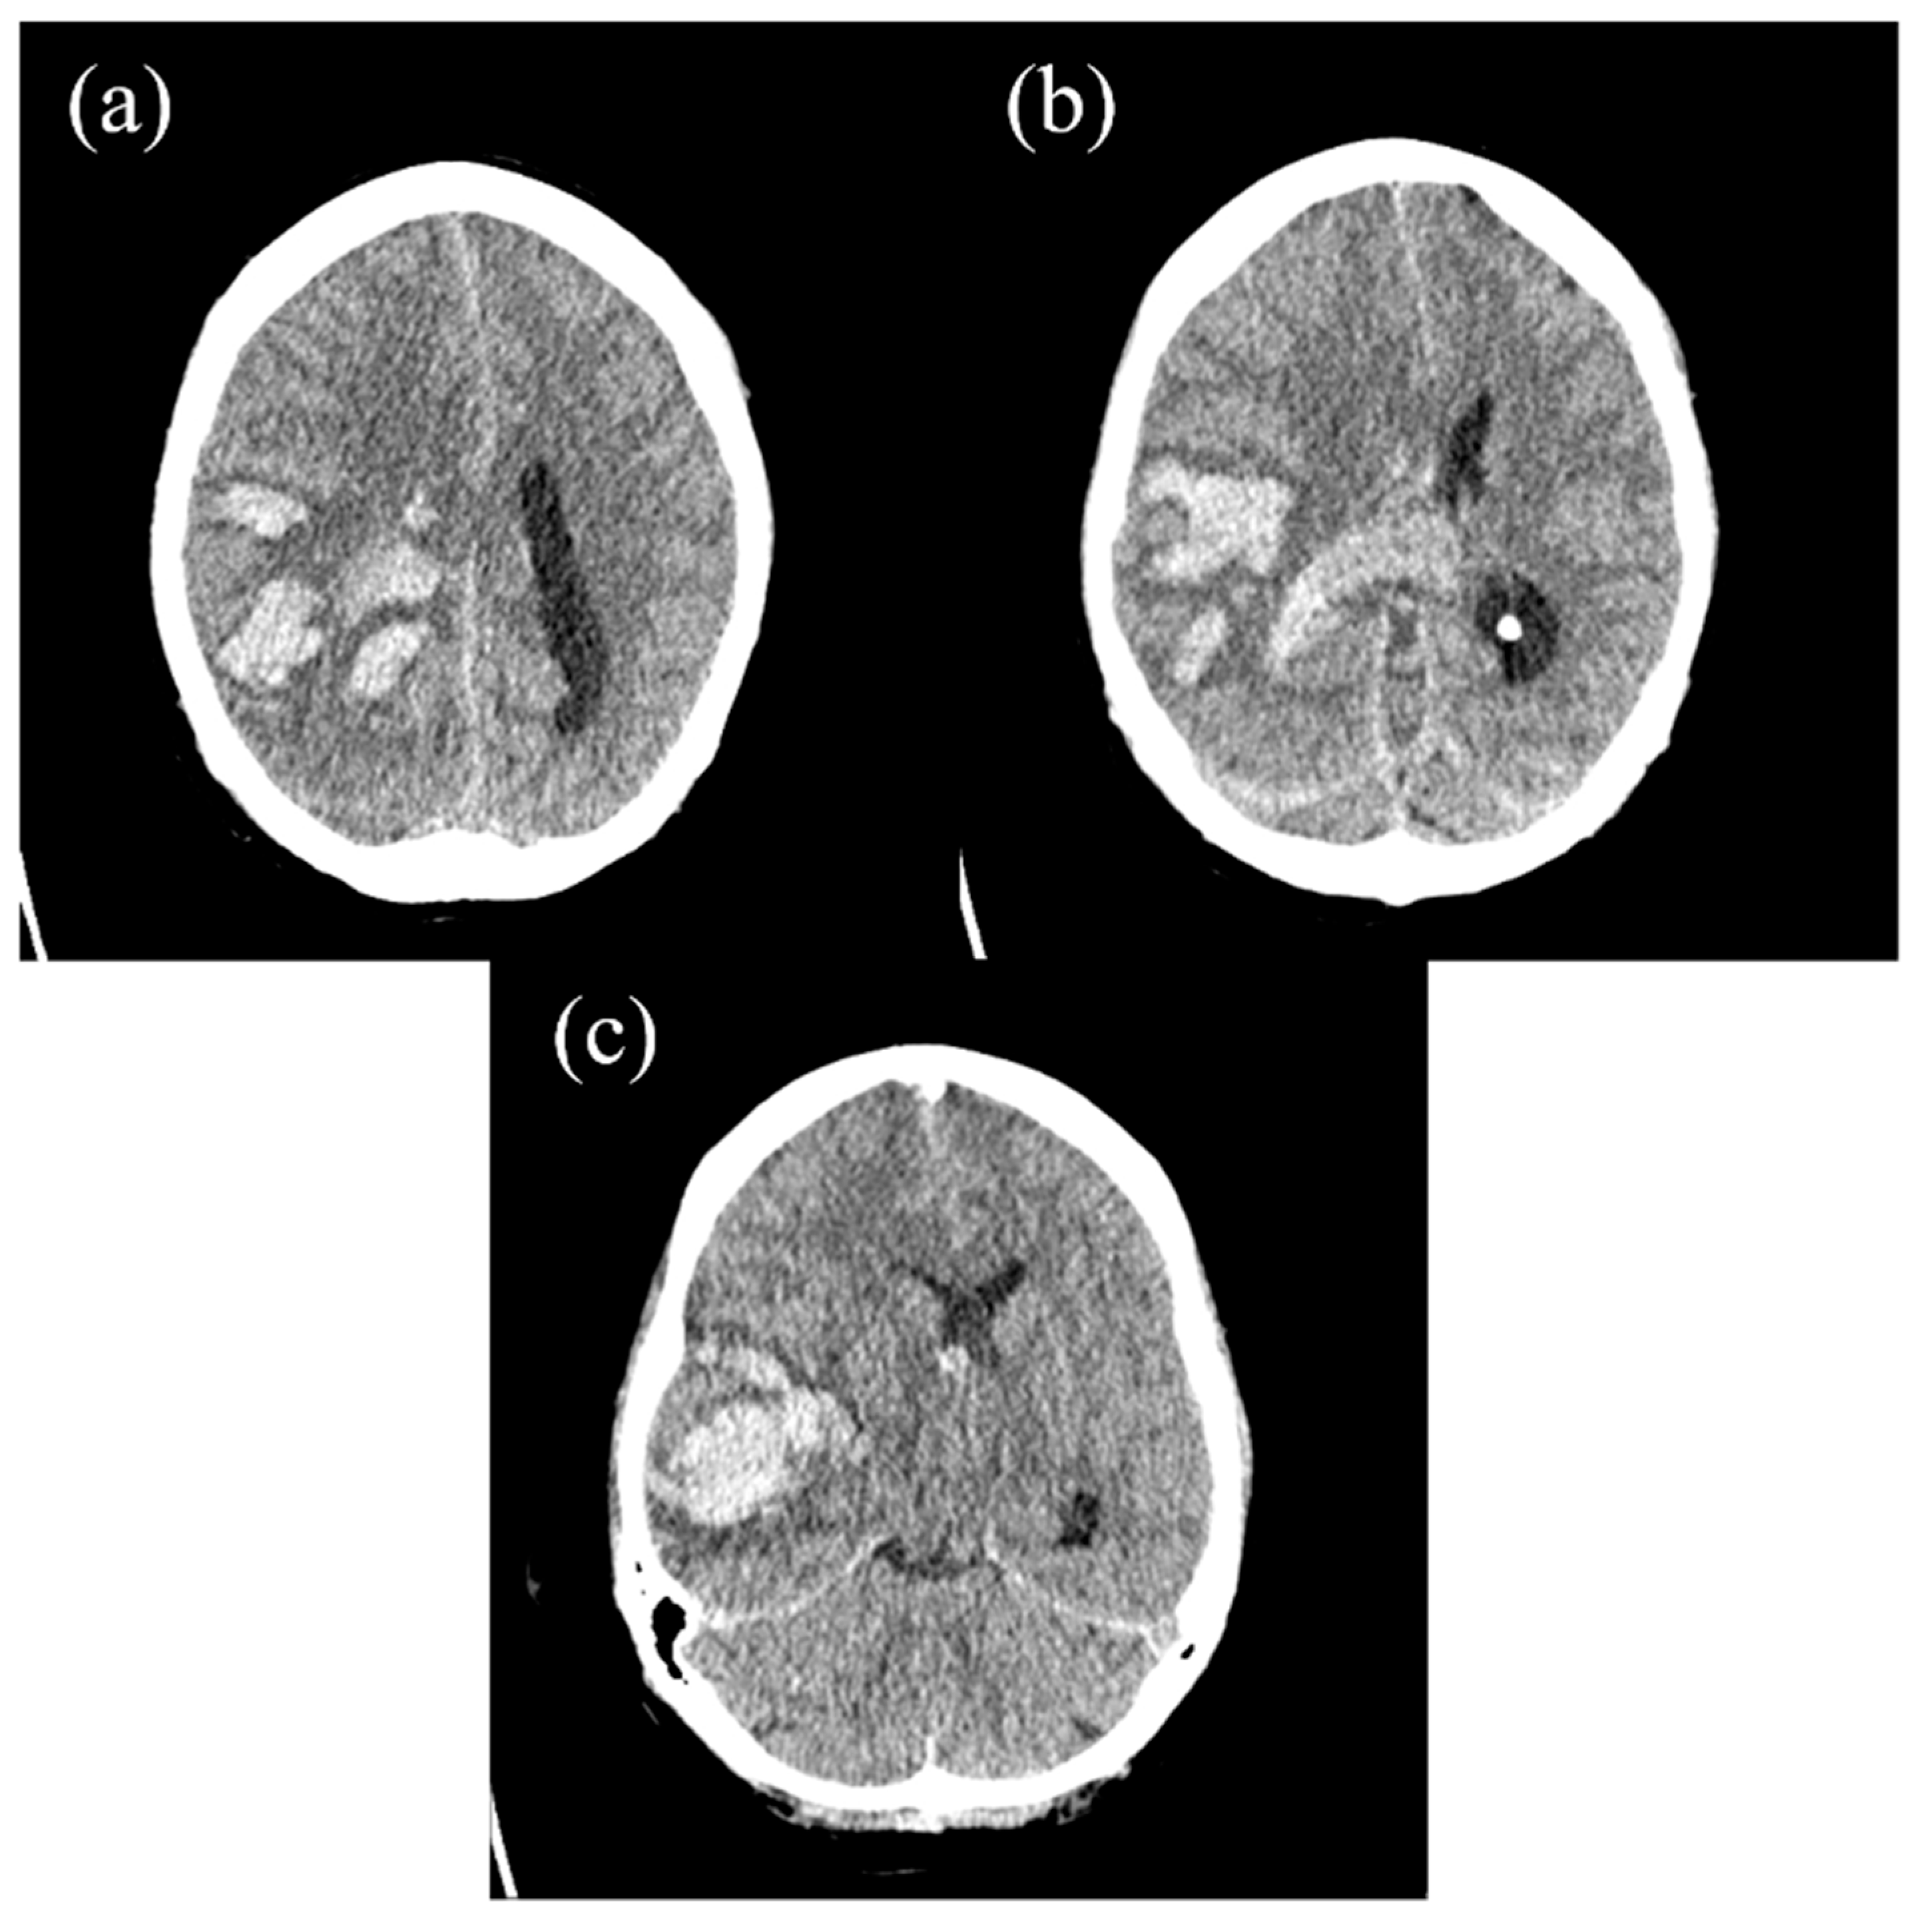

2. The Case Report